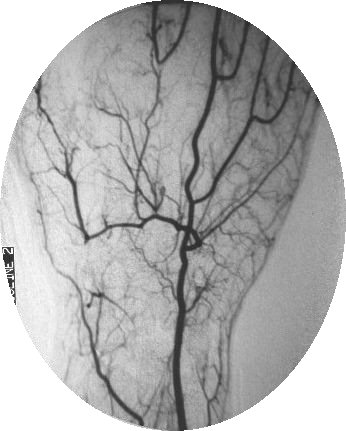

Case 3: More focal problem, thumb and index ischemia: Arteriogram:

Click for larger image